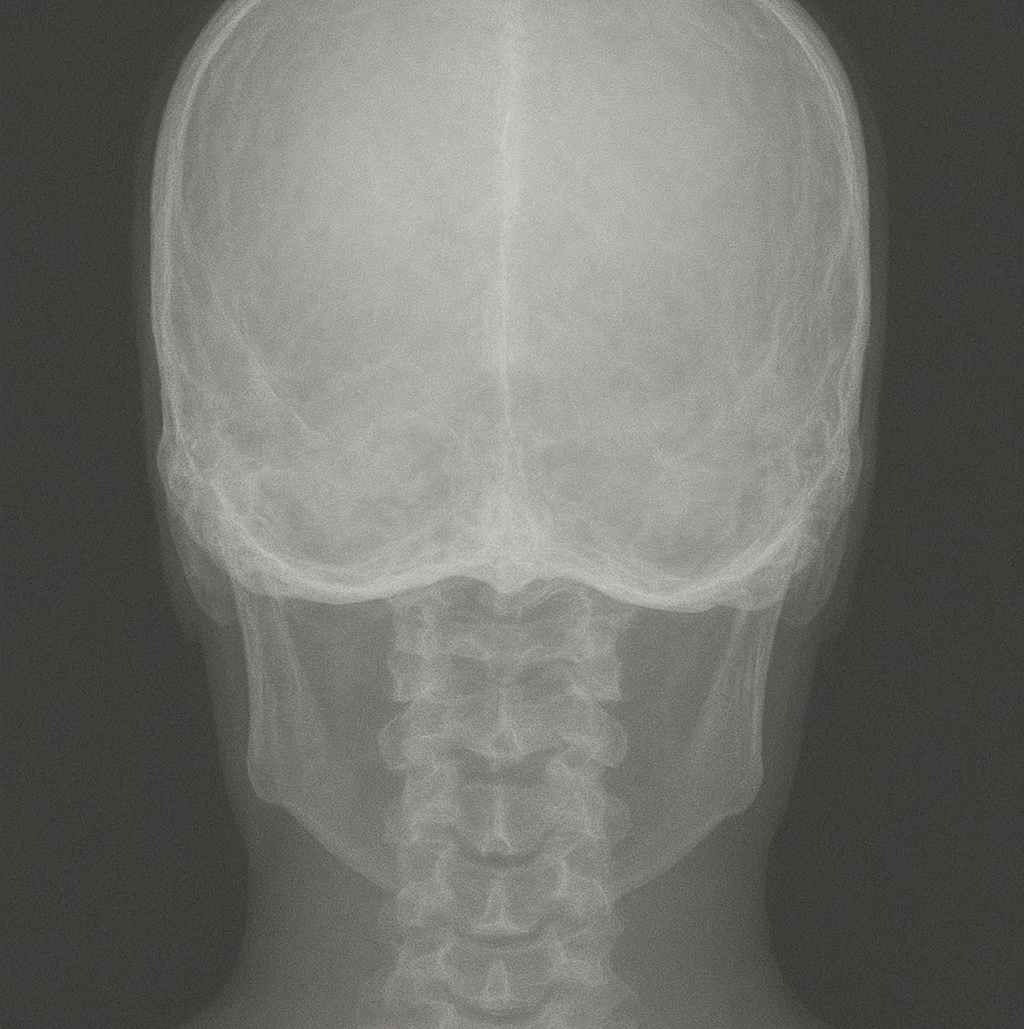

L’ematoma è una raccolta di sangue al di fuori di un vaso sanguigno, come arterie, vene o capillari, che si verifica normalmente in seguito a un trauma. Quando la parete di un vaso sanguigno si rompe, il sangue si accumula nei tessuti circostanti dando vita a questo fenomeno. Senza meccanismi di coagulazione adeguati, anche lesioni di lieve entità potrebbero essere fatali. Le persone con patologie della coagulazione, come l’emofilia, sanno bene i rischi legati alla formazione di ematomi.

Nelle normali condizioni fisiologiche, quando si verifica un danno alla parete vascolare, le fibre di collagene e i fattori di coagulazione del sangue si attivano per formare un coagulo che blocca la fuoriuscita di sangue. L’ematoma è quindi il risultato di una fuoriuscita di sangue che non viene riassorbita dal corpo.